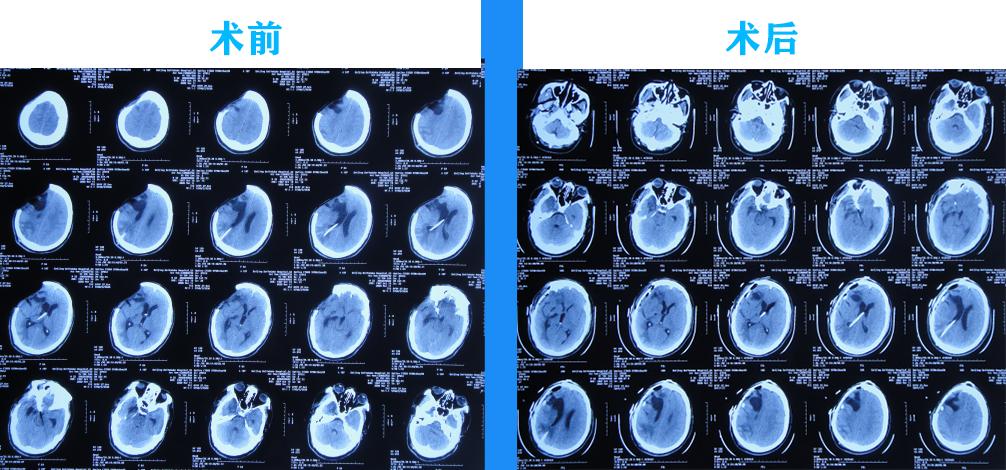

2020年3月11日(住院治疗36天),进行了颅骨修补术,留置脑室外外引流管,术前术后头颅CT(图-19)。

图-19:2020年3月11日术前术后头颅CT

2020年3月13日(住院治疗38天即颅骨修补术后2天),引流出血色脑脊液(图-20),头颅CT示积血减少,水肿减轻(图-21)。

图-21:2020年3月13日头颅CT